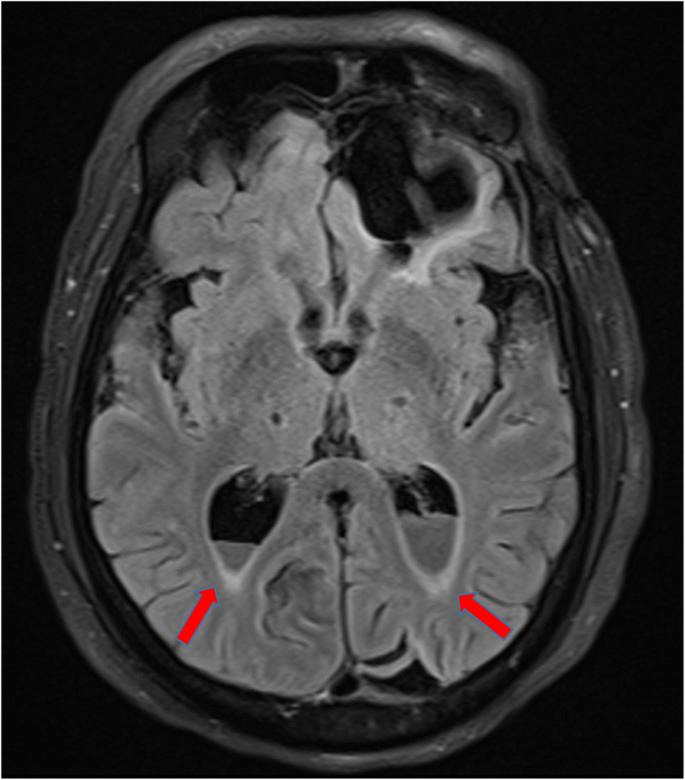

In accordance with the culture and sensitivity pattern, ceftriaxone was continued and amoxycillin was stopped. He was afebrile for the next 48 h, and his sensorium improved. Further work up was done to identify the source of seeding of E. coli to the meninges. Urine culture and blood cultures that were sent prior to initiation of antibiotics did not show any bacterial growth, and stool microscopy was negative for ova and cysts. CT scan of the abdomen revealed a non-obstructive renal calculus of 6 mm × 6mm at interpole of the left kidney without any signs of pyelonephritis. After the initial improvement, patient again had a drop in sensorium without any localizing signs. Magnetic resonance imaging (MRI) of the brain with contrast study was done to rule out secondary complications associated with meningitis like vascular infarcts or hydrocephalus. There was post-contrast enhancement of leptomeninges and subtle enhancement of ventricular wall and posterior fossa cisternal spaces in post-contrast T1 sequence, and the same findings along with exudates in the ventricles in T2 fluid attenuated inversion recovery (FLAIR) images, which were suggestive of ventriculitis (Figs. 4 and 5). CT cisternogram was performed to check for residual CSF leak at the past surgical site, in which there was an opacified density in the left frontal region representing a porencephalic cyst communicating with the left frontal horn. There was no CSF leak into the paranasal sinuses or nasal cavity (Fig. 6).